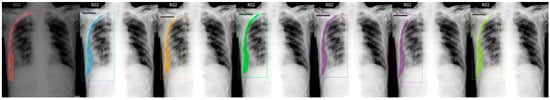

Figure 6.

From left to right: Ground Truth, ResNet50 (COCO), ResNet101 (COCO), ResNeXt101 (COCO), ResNet50 (LVIS), ResNet101 (LVIS), and ResNeXt101 (LVIS). This patient had pneumothorax in their right chest.

Figure 7.

From left to right: Ground Truth, ResNet50 (COCO), ResNet101 (COCO), ResNeXt101 (COCO), ResNet50 (LVIS), ResNet101 (LVIS), and ResNeXt101 (LVIS). This patient had pneumothorax in their left chest while having a fixation due to a probable accident.

We chose a few examples to demonstrate the capabilities of various models. These images consisted of X-ray images of pneumothorax patients with different areas of disease inflicted. The inclusion of multiple positions and areas in the figures lets us observe the possible outcomes and the differences between the models. In Figure 3 and Figure 6, the patients had pneumothorax on the right side of their chest, with the patient in Figure 6 only affecting the top part, while the patient in Figure 3 had pneumothorax on the outside wall of their right lung. In Figure 4, Figure 5 and Figure 7, the patients had pneumothorax in the left side of their chest, while the patients in Figure 4 and Figure 5 had the upper part of their left lung mostly collapsed, indicating a serious issue of pneumothorax disease. In Figure 5, there are cavity areas at the bottom part, too. In the same image, the ground truth included a portion protruding below the area of the top detection portion due to the late-stage pneumothorax with most of the upper part of the lung collapsing, and all models were unable to detect the cavity of the protruded part. In Figure 7, the patient is seen with a fixation, with the pneumothorax affecting the top left lung, albeit with a smaller area.